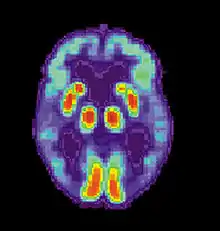

Human immunodeficiency virus (HIV)

Neural systems used by procedural memory are commonly targeted by Human Immunodeficiency Virus; the striatum being the structure most notably affected.[64] MRI studies have even shown white matter irregularity and basal ganglia subcortical atrophy in these vital areas necessary for both procedural memory and motor-skill.[65] Applied research using various procedural memory tasks such as the Rotary pursuit, Mirror star tracing and Weather prediction tasks have shown that HIV positive individuals perform worse than HIV negative participants suggesting that poorer overall performance on tasks is due to the specific changes in the brain caused by the disease.[66]